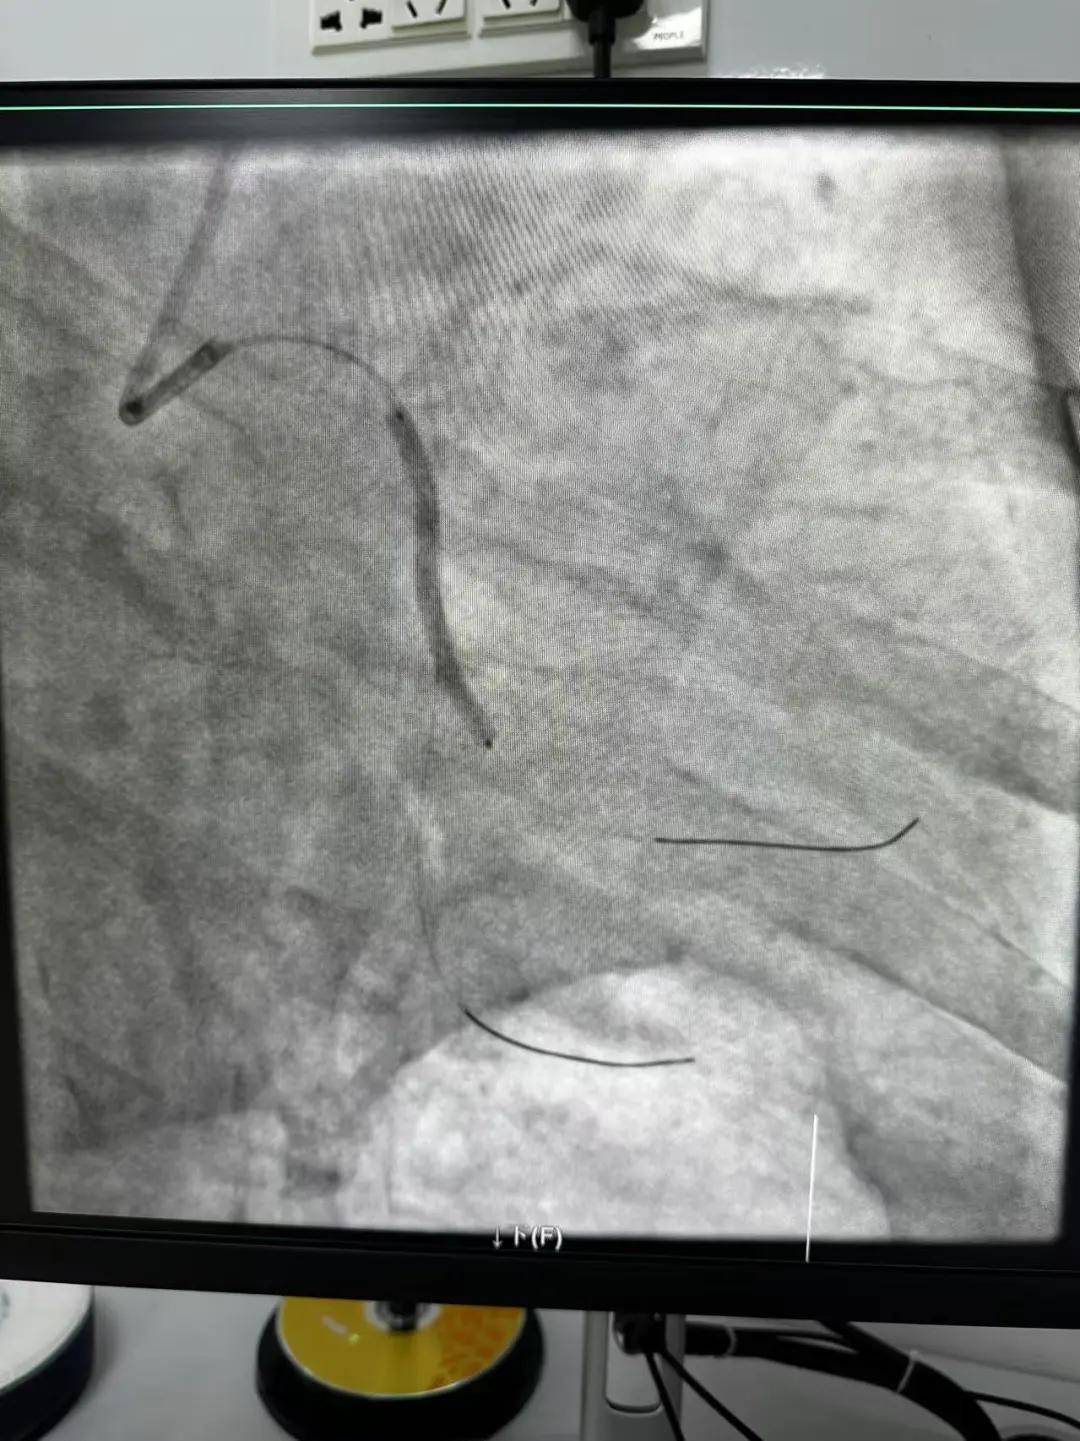

時間就是生命,時間就是心肌,救治刻不容緩。王云峰主任立即啟用第二個手術(shù)間進行“雙開臺”!將現(xiàn)有人員兵分兩路,兩路人馬各司其職,兩條救心“高速路”為患者火速同時搭建起來。副院長趙清亮也趕到導(dǎo)管室,親自坐鎮(zhèn)指揮。

穿刺、造影、放支架……兩個手術(shù)間各個環(huán)節(jié)緊張卻有序地進行著!在心內(nèi)科團隊精準、默契的配合下,兩臺手術(shù)順利完成! 兩名患者的快速、同時、成功救治,得益于殷都區(qū)人民醫(yī)院醫(yī)務(wù)人員快速的應(yīng)急能力、過硬的急救技能,同時更得益于導(dǎo)管室同開臺,保障了救治的迅速有效。